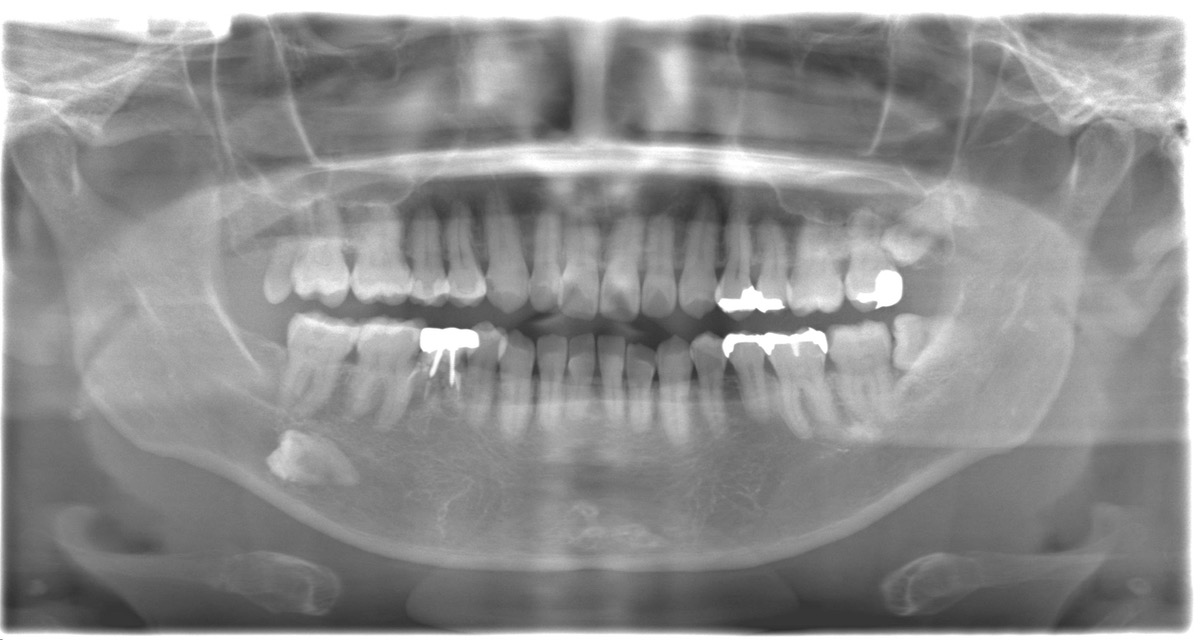

右下に永久歯が生えてこなかった場所に乳歯が残っていて、なんとかごまかし使ってきたが限界を迎えたので治してほしいと希望された患者様【50代男性】

ご相談内容 右下の永久歯がもともと生えておらず、乳歯がそのまま残っていた。長年問題なく使ってきたが、最近ぐらつきと歯ぐきの減少が進み「もう限界ではないか」と不安になり来院。

レントゲンを確認しました。確かに永久歯が存在せず、乳歯が残っていますね。成人まで残ること自体はありますが、50代になると耐久的に厳しくなることが多いです。

残念ながら、この乳歯は根が短く、周囲の骨も減ってきています。長期的に残すのは難しい可能性が高いです。